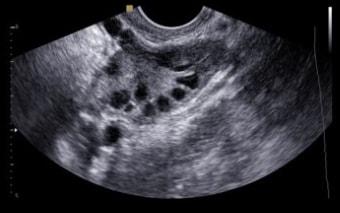

Определение количества сферических образований в яичниках осуществляется во многих медицинских учреждениях, ориентированных на женское здоровье. В процессе обследования специалист по лабораторной диагностике учитывает лишь те фолликулы, которые можно четко визуализировать.

Однако многие образования могут оставаться незамеченными из-за их небольшого размера или недостаточной точности используемого оборудования. Обычно неучтенные фолликулы рассматриваются как незначительная погрешность, не влияющая на итоговые результаты исследования. Для повышения достоверности подсчета рекомендуется проводить анализ на второй или третий день менструального цикла.

Индикатор фертильности: Количество и качество антральных фолликулов в яичниках служат важным индикатором фертильности женщины. Ультразвуковое исследование может помочь оценить их количество, что позволяет врачам делать выводы о репродуктивном здоровье и планировании беременности.

Количество антральных фолликулов в яичниках является индикатором овариального резерва, то есть способности яичников производить яйцеклетки. Исследования показывают, что снижение числа антральных фолликулов может быть связано с возрастом, гормональными нарушениями и различными заболеваниями, такими как поликистоз яичников. Оценка антральных фолликулов с помощью ультразвукового исследования позволяет врачам получить информацию о состоянии репродуктивной системы женщины и предсказать вероятность успешного зачатия.

Состояние антральных фолликулов можно оценить с помощью ультразвукового исследования (УЗИ) яичников, которое позволяет визуализировать количество и размер фолликулов. Также могут использоваться гормональные анализы, такие как уровень ФСГ (фолликулостимулирующего гормона) и эстрадиола, для оценки функции яичников и общего репродуктивного здоровья.